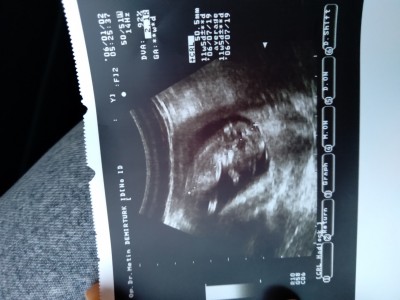

cinsiyet tahmini yapablen varmi 11+5

Erkek gecti içimden canim ya

Kıza benzettim ben

Kız olcakkk :D

06.07.19

yaziyor tariih çok eski :////

Kız daha az once geldim hastaneden cihaz eskidir ondandr

O tarih değil sanırım üstte de ona benzer sayılar var.

Usg cihazı bayağı geride kalmış. Tarih canim o kendi usg baktim.tarih yaziyor o bölümlerde:))

Bu kağıda göre hissim erkek :)))

Erkek geçti icimden vala